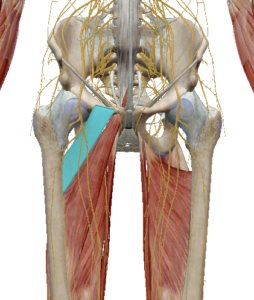

(2) 대둔근

대군근은 장골과 엉치뼈를 지나며 대퇴골에 연결되어 있습니다.

고관절의 신전과 외회전을 발생시킵니다.

(3) 중둔근과 소둔근

중둔근은 고관절 측면 안정성에 중요한 근육입니다.

수축 시 고관절 외전과 섬유의 위치에 따라 내회전과 외회전도 관여한다고 합니다.

소둔근도 중둔근과 같이 고관절 측면 안정성에

중요한 역할을 합니다.

고관절 외전을 발생시키며 고관절 앞쪽에 연결되어 있어 고관절 굴곡과 내회전을 발생합니다.

(4) 이상근

이상근은 천골의 앞쪽에서 부터 대퇴골의 위쪽을 향하고 있습니다.

고관절을 외회전 시키며 이상근 아래로 좌골신경이 지나가면서 좌골신경통의 원인으로 주목받고 있습니다.

이상근이 주목받는 또 다른 이유로는 기능의 변화입니다.

이상근은 고관절이 90도 이상 굴곡될 경우 고관절 내회전으로 기능이 변화합니다.

이는 근육의 기능은 해부학적 자세에서 기록된 것이며 자세에 따라 다르게 작용할 수 있다는 근거가 됩니다.